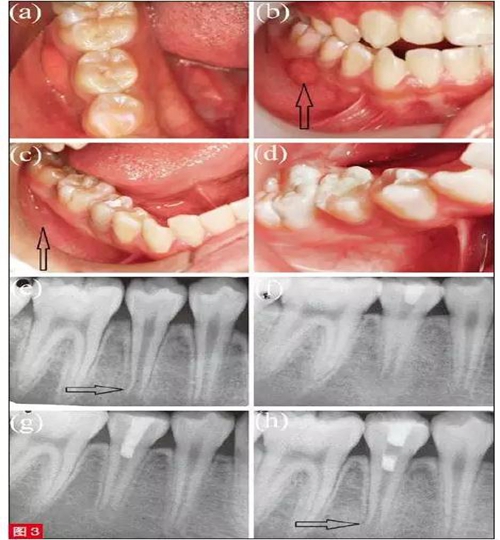

患者為9 歲男童,主訴右側(cè)牙齒咀嚼痛2 周。6 個月前患者右下頜疼痛腫脹,當時未接受任何治療。臨床檢查,見45 牙畸形中央尖折斷,未見齲壞(圖3a),45 和46 間牙齦見竇道(圖3b)。45 叩診(+), II 度松動,冷測及EPT 測試均無反應(yīng)。根尖片示,牙根未發(fā)育完全,根尖孔敞開且根尖周見透射影(圖3e)。依照臨床和影像檢查,45 初步診斷為慢性根尖膿腫。由于牙根尚未發(fā)育完全、根尖孔敞開,推薦使用MTA 為其進行牙髓再生治療?;颊咧橥夂?,即刻治療。

具體治療過程如下:以2% 利多卡因(3MDeutschland GmbH,德國)局部浸潤麻醉45 牙,橡皮障隔離。高速渦輪手機在噴水冷卻下進行開髓。此時,根管冠方可見呈粉色、質(zhì)地連續(xù)的活髓組織。最終診斷為45 部分牙髓壞死伴慢性根尖膿腫。隨后切除冠部壞死牙髓組織,根管內(nèi)20ml 3%NaOCl 溶液沖洗3 分鐘,再使用10ml 生理鹽水沖洗3 分鐘。無菌紙尖干燥根管后,導(dǎo)入氫氧化鈣糊劑(圖3f),使用IRM 暫封材料(Dentsply Caulk, 美國)進行冠方封閉?;颊? 周后復(fù)診,述治療后未出現(xiàn)疼痛,臨床檢查,見頰側(cè)竇道完全消失(圖3c)。45 牙叩診(+-),且變?yōu)镮 度松動。在橡皮障隔離下,去除IRM 暫封材料,20ml 3%NaOCl 溶液沖洗3 分鐘,再使用10ml 生理鹽水沖洗3 分鐘,以完全清除氫氧化鈣糊劑。無菌紙尖干燥根管后,在活髓組織上放置MTA( ProRoot,Dentsply Tulsa Dental, 美國), 開髓孔由Cavit (GCCorp,日本)和玻璃離子水門汀分層封閉(圖3g)。8 個月后復(fù)查,45 牙無任何癥狀,叩診、捫診均無不適,冷測和EPT 測試顯示牙髓有活力,臨床檢查均表現(xiàn)正常。根尖片示牙根持續(xù)發(fā)育,根尖孔逐漸閉合,根尖周透射影完全消失,根管壁明顯增厚,且根尖孔縮窄(圖3h)。去除Cavit 暫封材料,使用復(fù)合樹脂永久充填(Filtek Z350 XT; 3M ESPE Dental Products,美國)(圖3d)。